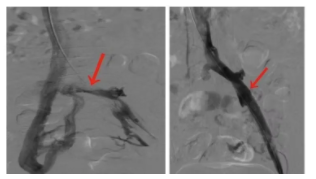

07.png

术前髂总静脉闭塞侧枝静脉开放

08.png

术后髂静脉通畅良好侧枝不再显示

11.png

左髂静脉闭塞开通并支架置入术后通畅良好

12.png

术前侧枝静脉开放术后消失